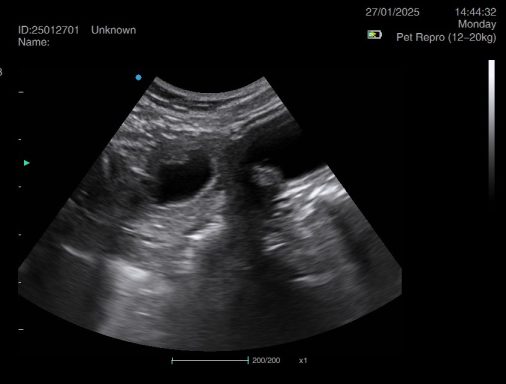

Ultrasound pregnancy scanning is a safe, non-invasive way to confirm pregnancy in dogs and cats, offering breeders and pet owners peace of mind and vital information to support responsible care. It allows us to detect gestational sacs, assess foetal development, and estimate litter size—all while ensuring the wellbeing of the animal.

Pregnancy can sometimes be detected as early as Day 18 post-mating, but scanning at this stage is not routinely recommended. Embryos are still developing and may not be clearly visible, and there is a natural risk of embryo resorption, which can lead to misleading or inconclusive results.

For the most accurate and reliable scan, we advise booking between Day 25 and Day 32, when pregnancy is more easily confirmed and foetal structures are clearer. If an early scan is performed and no pregnancy is detected, we offer a FREE complimentary re-scan after 7 days at the clinic to ensure clarity and support informed decision-making.

Our approach balances early insight with ethical care—always prioritizing the comfort of the animal and the accuracy of the results.

Gallery